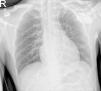

A 31-year-old male presented with alternating bifascicular block with symptomatic complete atrioventricular block and a normal echocardiogram. A permanent pacemaker was implanted through the left subclavian vein. Upon inserting the guidewire, a single persistent left superior vena cava (PLSVC) was identified and verified using phlebography and tomography. The PLSVC flows into the coronary sinus (CS), and into the right atrium (RA). The atrial and right ventricular (RV) active fixation electrodes were implanted retrogradely through the CS (see Figs. 1 and 2).